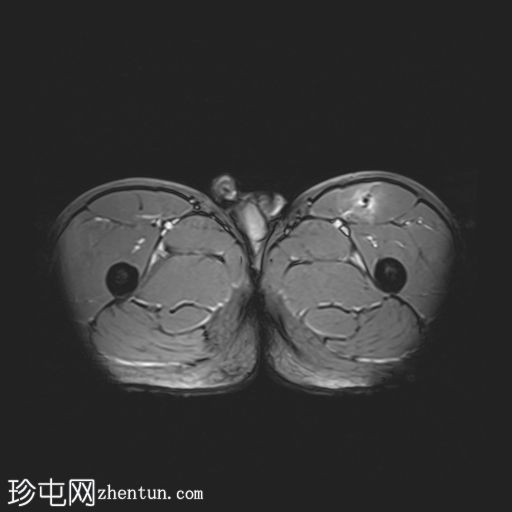

轴位

T1加权像

左侧股直肌近端肌腱交界处可见异常高信号,向远端延伸约至肌长一半。

可见清晰的充满液体的分离平面,呈“靶心征”,将双羽状间接头与浅表单羽状直接头分隔开,呈现出股直肌脱套样损伤的特征性影像

间接头肌纤维与近端肌腱保持连续,未见肌腱断裂或明显回缩。

可见轻度肌间及筋膜周围水肿。病例讨论